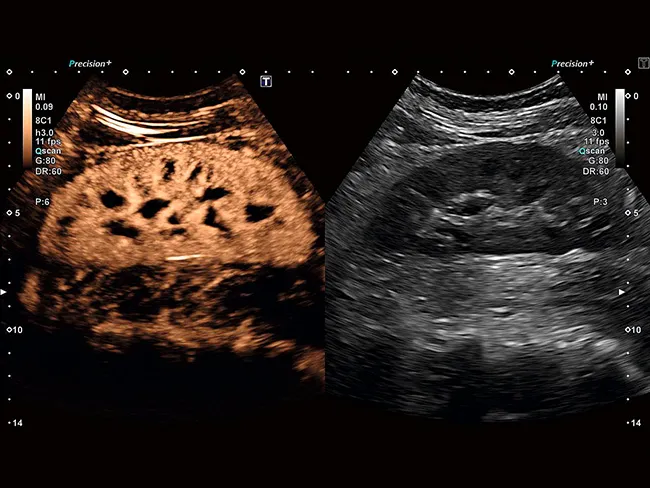

Precision + обеспечивает сглаженные изображения с четкими очертаниями контуров, повышенную однородность изображения и уменьшение помех.

ApliPure + обеспечивает повышенную контрастность изображения и уменьшение спекл-шума для улучшения визуализации.

Как занятый врач, так и пациент могут воспользоваться 2D-визуализацией высокого разрешения и объемным ультразвуковым исследованием. Комплексный пакет объемной визуализации Aplio расширяет ваши диагностические возможности и выходит на новый уровень визуализации благодаря исключительному качеству изображения и бескомпромиссному рабочему процессу.

Широкий спектр опций MultiView позволяет получать поперечные срезы с высоким разрешением, помогая лучше понять анатомические взаимосвязи или степень данного поражения.

Aplio обеспечивает цветную допплерографию с превосходным пространственным разрешением, позволяющую выявлять мельчайшие узоры кровотока с беспрецедентной точностью и детализацией при высокой частоте кадров, сохраняя при этом полное качество изображения в режиме B